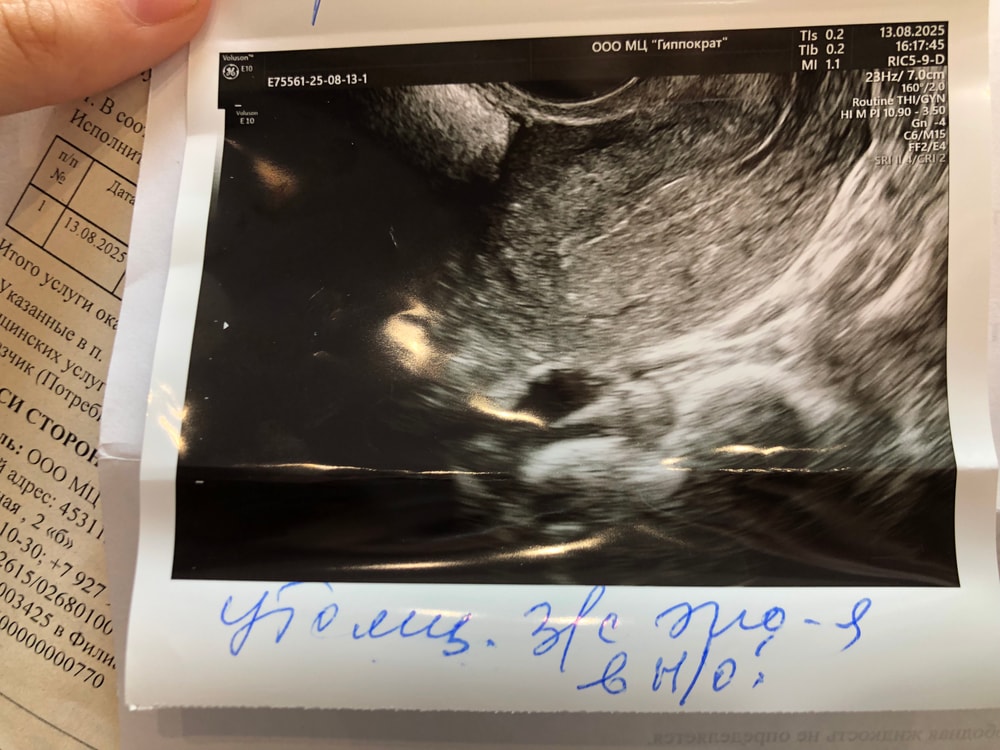

Эндометриома это эндометриоидная киста.

Но с теми размерами, что у вас - это ни о чем

Алиса , эндометриоидные кисты не рассасываются.

Размер у вас маленький, если это эндометриоидная киста такого размера - то поводов переживать нет, если не будет расти.